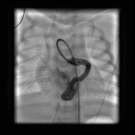

A 20-year-old woman presented for her first prenatal care visit at 32 weeks of gestation. Her pregnancy had been uneventful. An initial fetal ultrasonogram demonstrated an enlarged heart and aortic...

Due to a neonate’s tachypnea and pallor at delivery, echocardiography was done to assess for cardiac lesions, only to find one of the rarest conditions known of cardiac origin, of which requires serious...